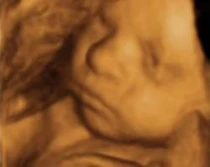

Texas: Firman ley que obliga a realizarse ultrasonido antes de aborto

27 de may. de 2011

El gobernador de Texas (Estados Unidos), Rick Perry, firmó el Proyecto de Ley 15, que entraría en vigor en septiembre,... Leer más